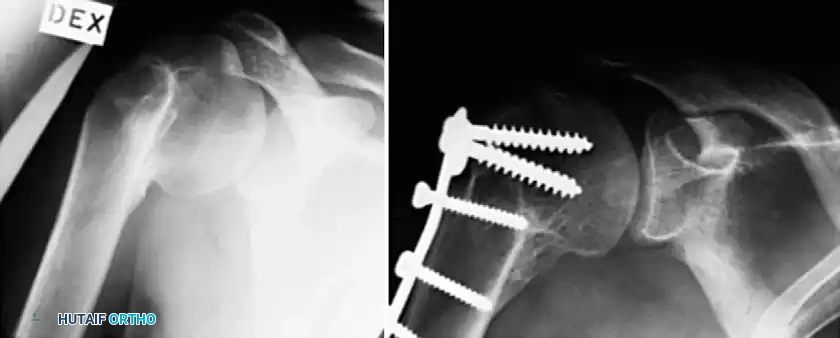

Surgical intervention is indicated for severe, intractable pain or profound functional loss that has failed conservative management. The choice of procedure depends heavily on the status of the articular cartilage, the viability of the humeral head, and the chronicity of the malunion.

- Joint-Preserving Reconstruction: Includes acromioplasty, lysis of adhesions, and corrective osteotomies of the tuberosities or surgical neck. This is indicated only if the blood supply to the humeral head is intact and the articular surface is preserved. Acromioplasty alone may suffice for greater tuberosity displacement of 1 to 1.5 cm, whereas formal osteotomy and mobilization are required for displacement >1.5 cm.

- Arthroplasty (Hemiarthroplasty or Total Shoulder Arthroplasty): Indicated for extensive articular damage, severe incongruity, or established osteonecrosis. The choice between hemiarthroplasty and TSA depends on the status of the glenoid cartilage and the rotator cuff.

Plate Fixation and Grafting

Associated Surgical & Radiographic Imaging